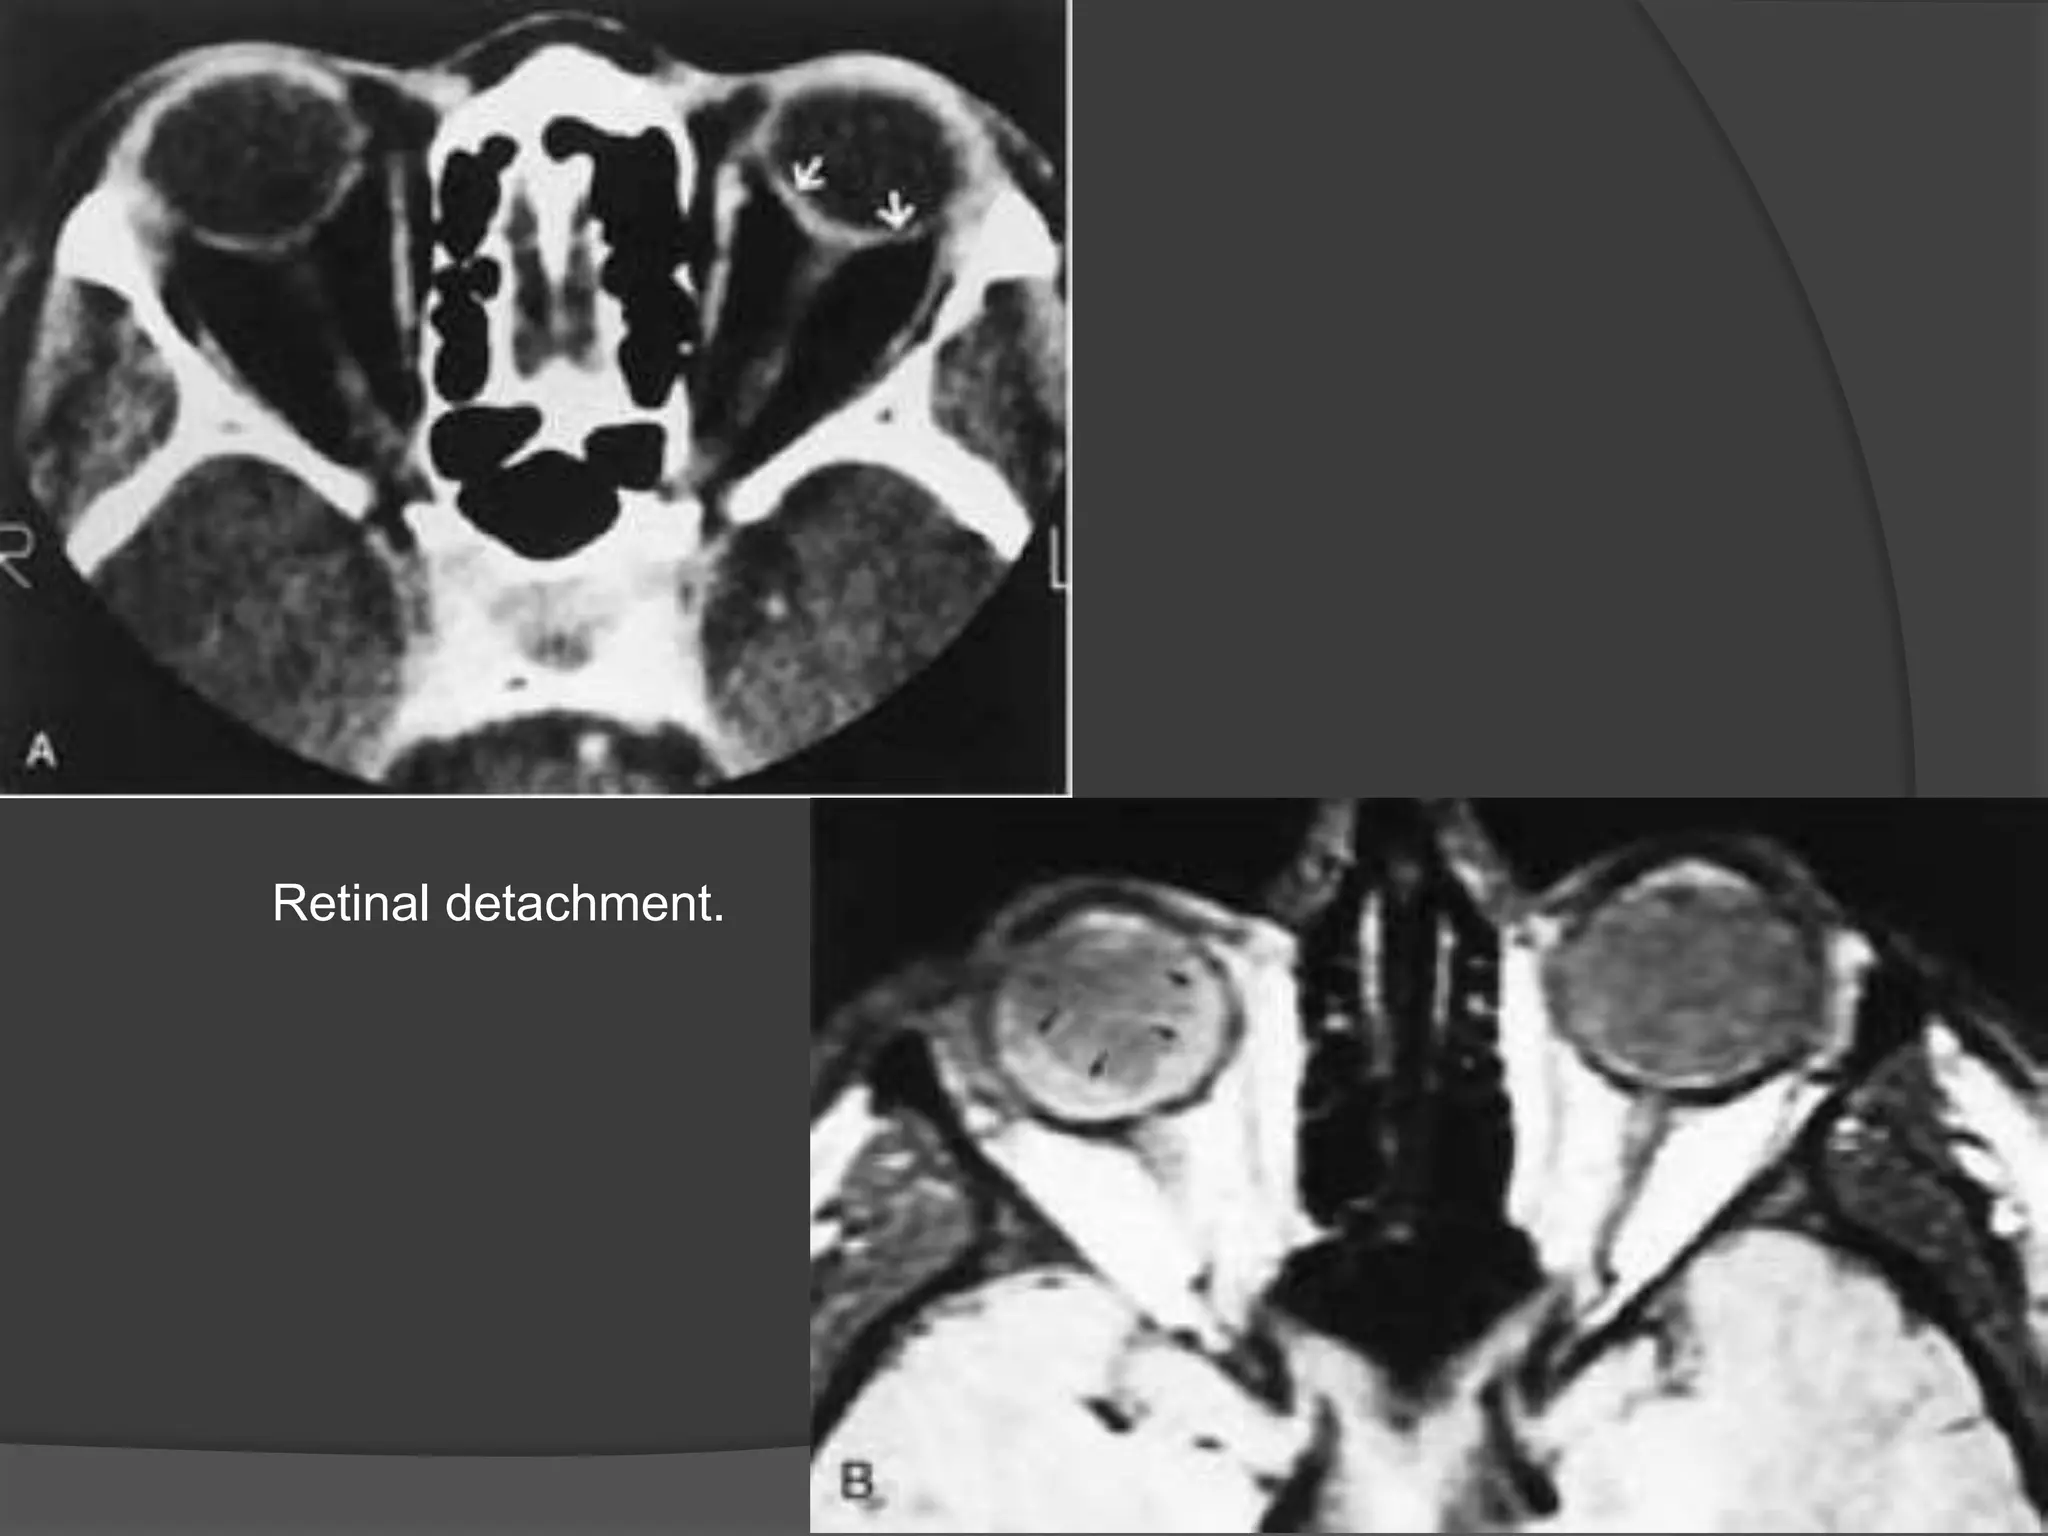

Ocular detachments

Retinal detachment.

• #12 Retinal detachment. A - White arrows is retinal detachment B – Black arrows – hyperintense areas - subretinal exudate

• #14 Retinal detachment. T1-weighted coronal MR image shows the characteristic appearance of retinal folds (arrows) and a hyperintense subretinal exudate (E ).